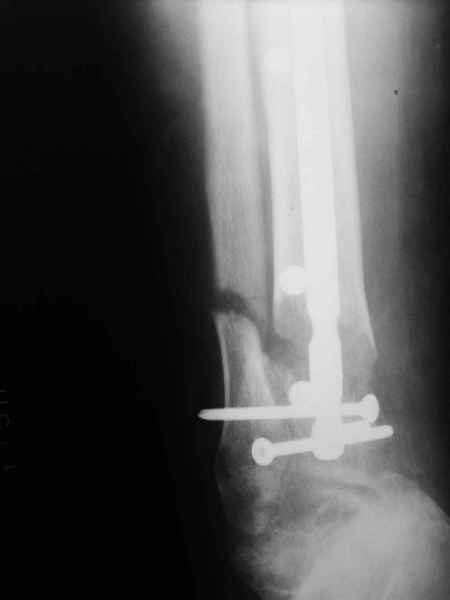

[Ortho] Метатарзал краш синдром в порочном сращении (эквинусная стопа), несращение сегментарного перелома костей голени после БИОС , ПТФБ, ХВН СЕАР С-6.

уважаемые коллеги помогите как с этим разобраться